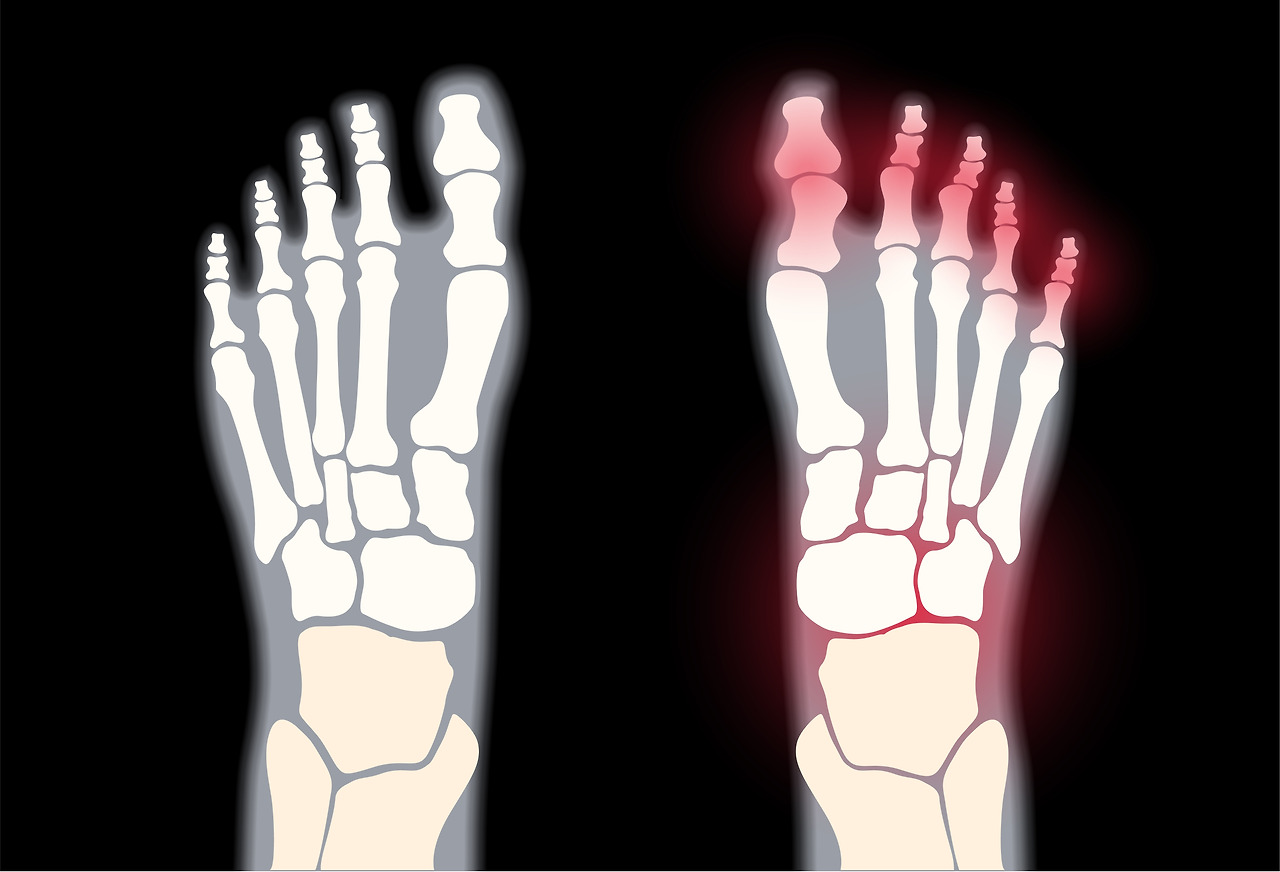

족부 클리닉

● 담당: 일산백병원 정형외과 서진수 교수

노령인구 증가 및 식습관 변화로 인한 당뇨병의 증가와 스포츠 인구의 증가등으로 족부질환에 관한 관심이 급격히 증가하고 있으며 기능개선과 함께 미용적 관점을 최대한 고려하여 치료 하고 있습니다. 이상과 같이 지역 사회 의료 발전에 중추적인 역할을 담당 하고 있습니다.